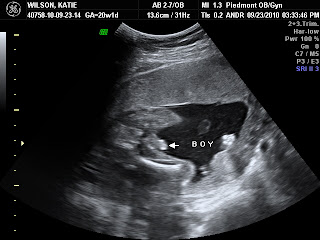

20 Week appointment went great! We definitely have a boy and he is doing great! I'm feeling him move around a good bit now, which is definitely a new experience. We got alot of pictures this time: